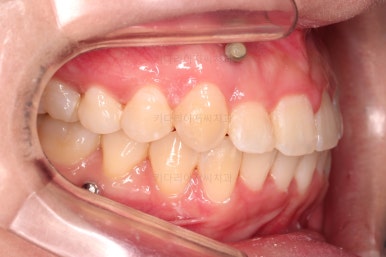

1. 초진

초진 시 입안의 모습입니다.

전반적으로 치열이 삐뚤고요.

위아래 중앙선이 약간 틀어져 있는데 많이 심한 편은 아니고요. 윗니가 배열된 U자 형태를 보면 아랫니보다 좁은 형태로 "악궁이 좁은" 상황이었습니다.